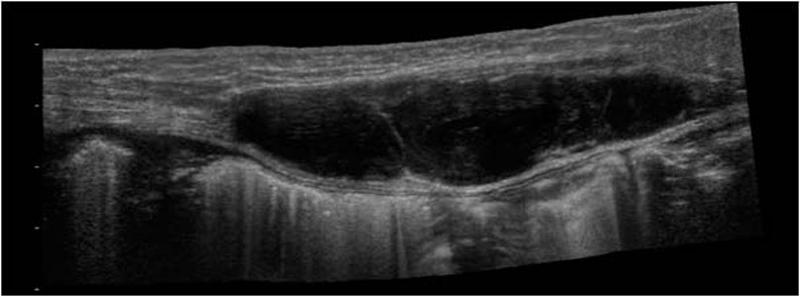

Achilles Tendon Rupture

inability to extend knee

Patellar tendon Rupture